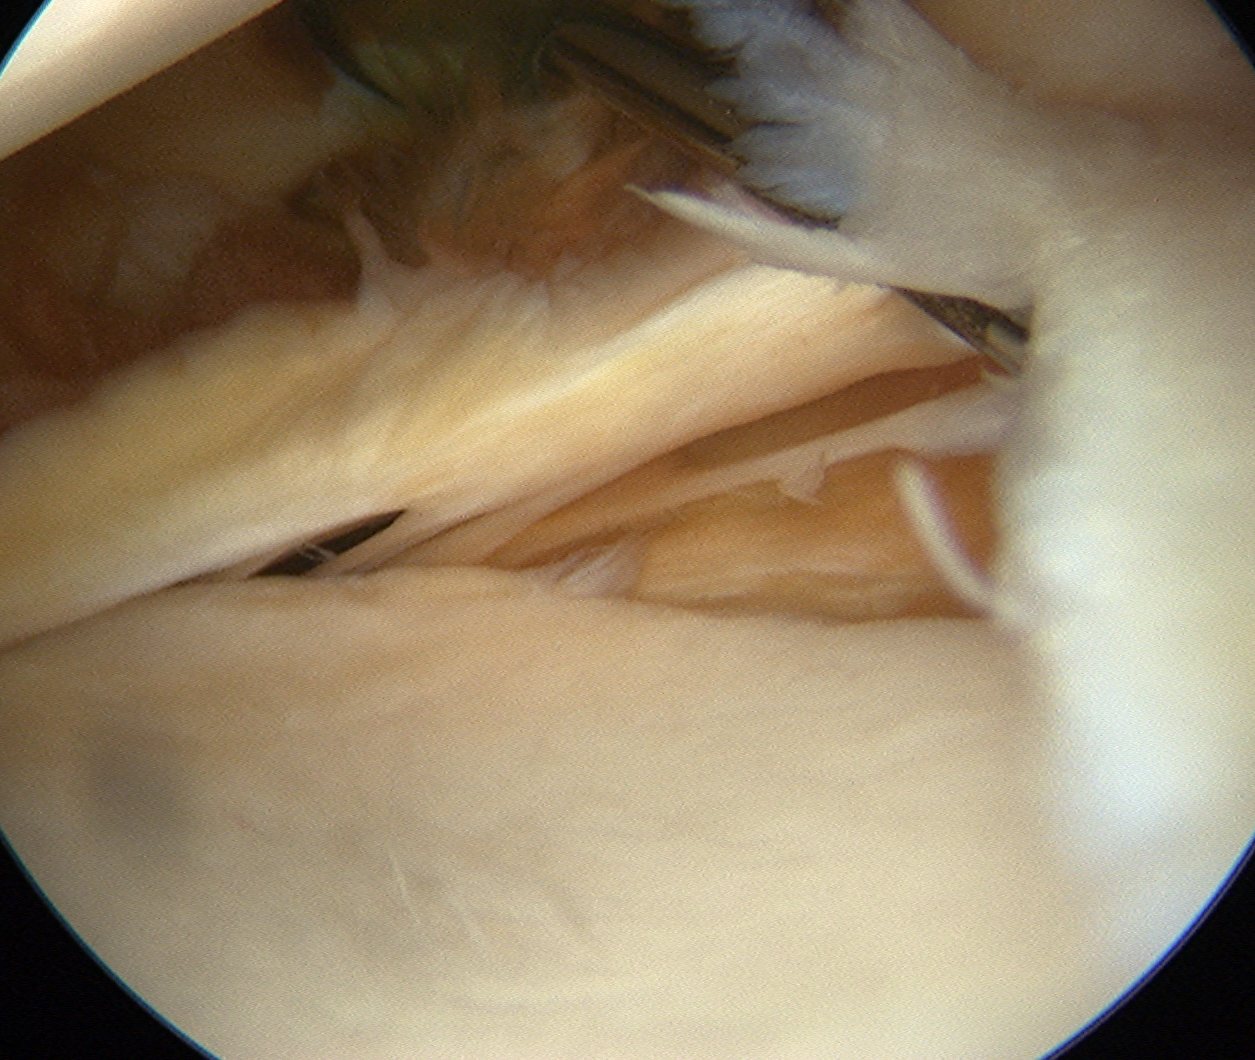

Technique arthroscopic anterior labral / Bankart repair

Steps

Insert anchors

Inferior anchor at 5.30 o'clock

- curved anchor guide / trans-subscapularis

- on rim of glenoid

Other anchors typically at 3 and 4 o'clock

Pass sutures and tie knots

Typically curved suture passers

Aim to tighten capsule medially and superiorly onto glenoid